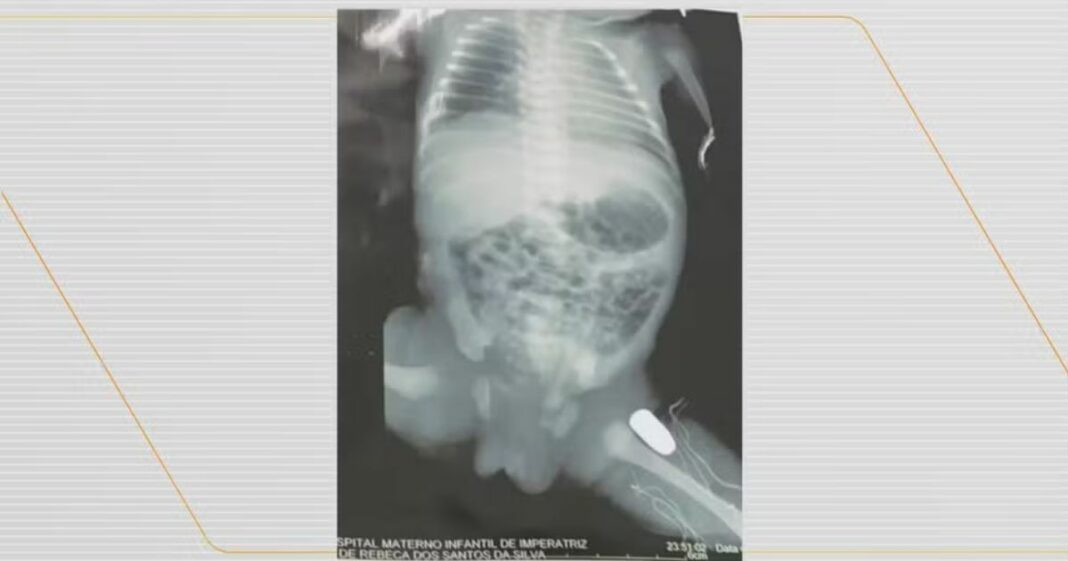

Uma bebê de 32 semanas de gestação, que foi atingida por um tiro dentro da barriga da mãe, uma adolescente de 15 anos, na cidade de Imperatriz, foi submetida a uma cirurgia para remoção do projétil da perna esquerda.

Os tiros atingiram a barriga da adolescente, que foi socorrida e levada para a Maternidade de Alto Risco de Imperatriz, onde passou por uma cesárea de emergência. Exames de imagem mostraram que um dos tiros atingiu a perna esquerda do bebê.